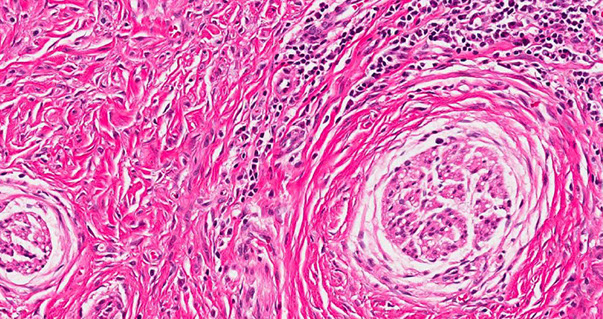

Sclerotic fibroma

May be clue for Cowden syndrome

"starry night" or "plywood" storiform pattern of collagen, hypocellular with bland nuclei